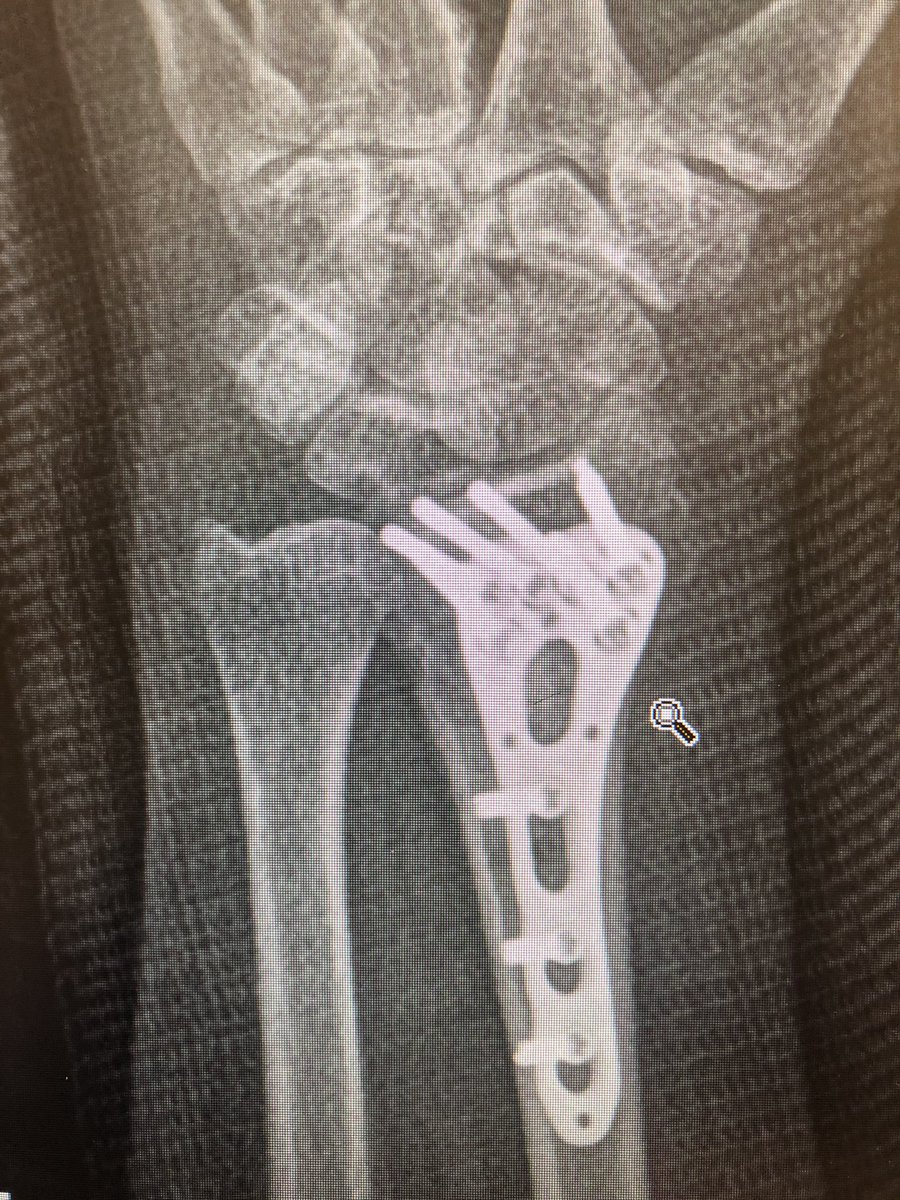

Point 1:

The proximal fragment radius spike has a risk of translational mal-reduction and this can bother rotation of the forearm.

Reduce this by putting a ‘lamina spreader’ in the inter-osseus space Before locking the shaft screws and clear the DRUJ.

Point 2:

The dorsal metaphyseal comminution. The dorsal cortex fragment is ‘fallen in’ inside the osteoporotic metaphyseal void.

I addressed this after plating finished, made a 4.5 mm drill hole in the ‘window’ of the plate to push the fragment and fill in graft substitute.

This was the patient at 2 weeks. Already on range of motion. The flat lateral X-ray always looks like the screws are in the joint. That’s because of the distal radius joint inclination angle.

Take intra-operative 20 degree elevated lateral shot to see through the joint.